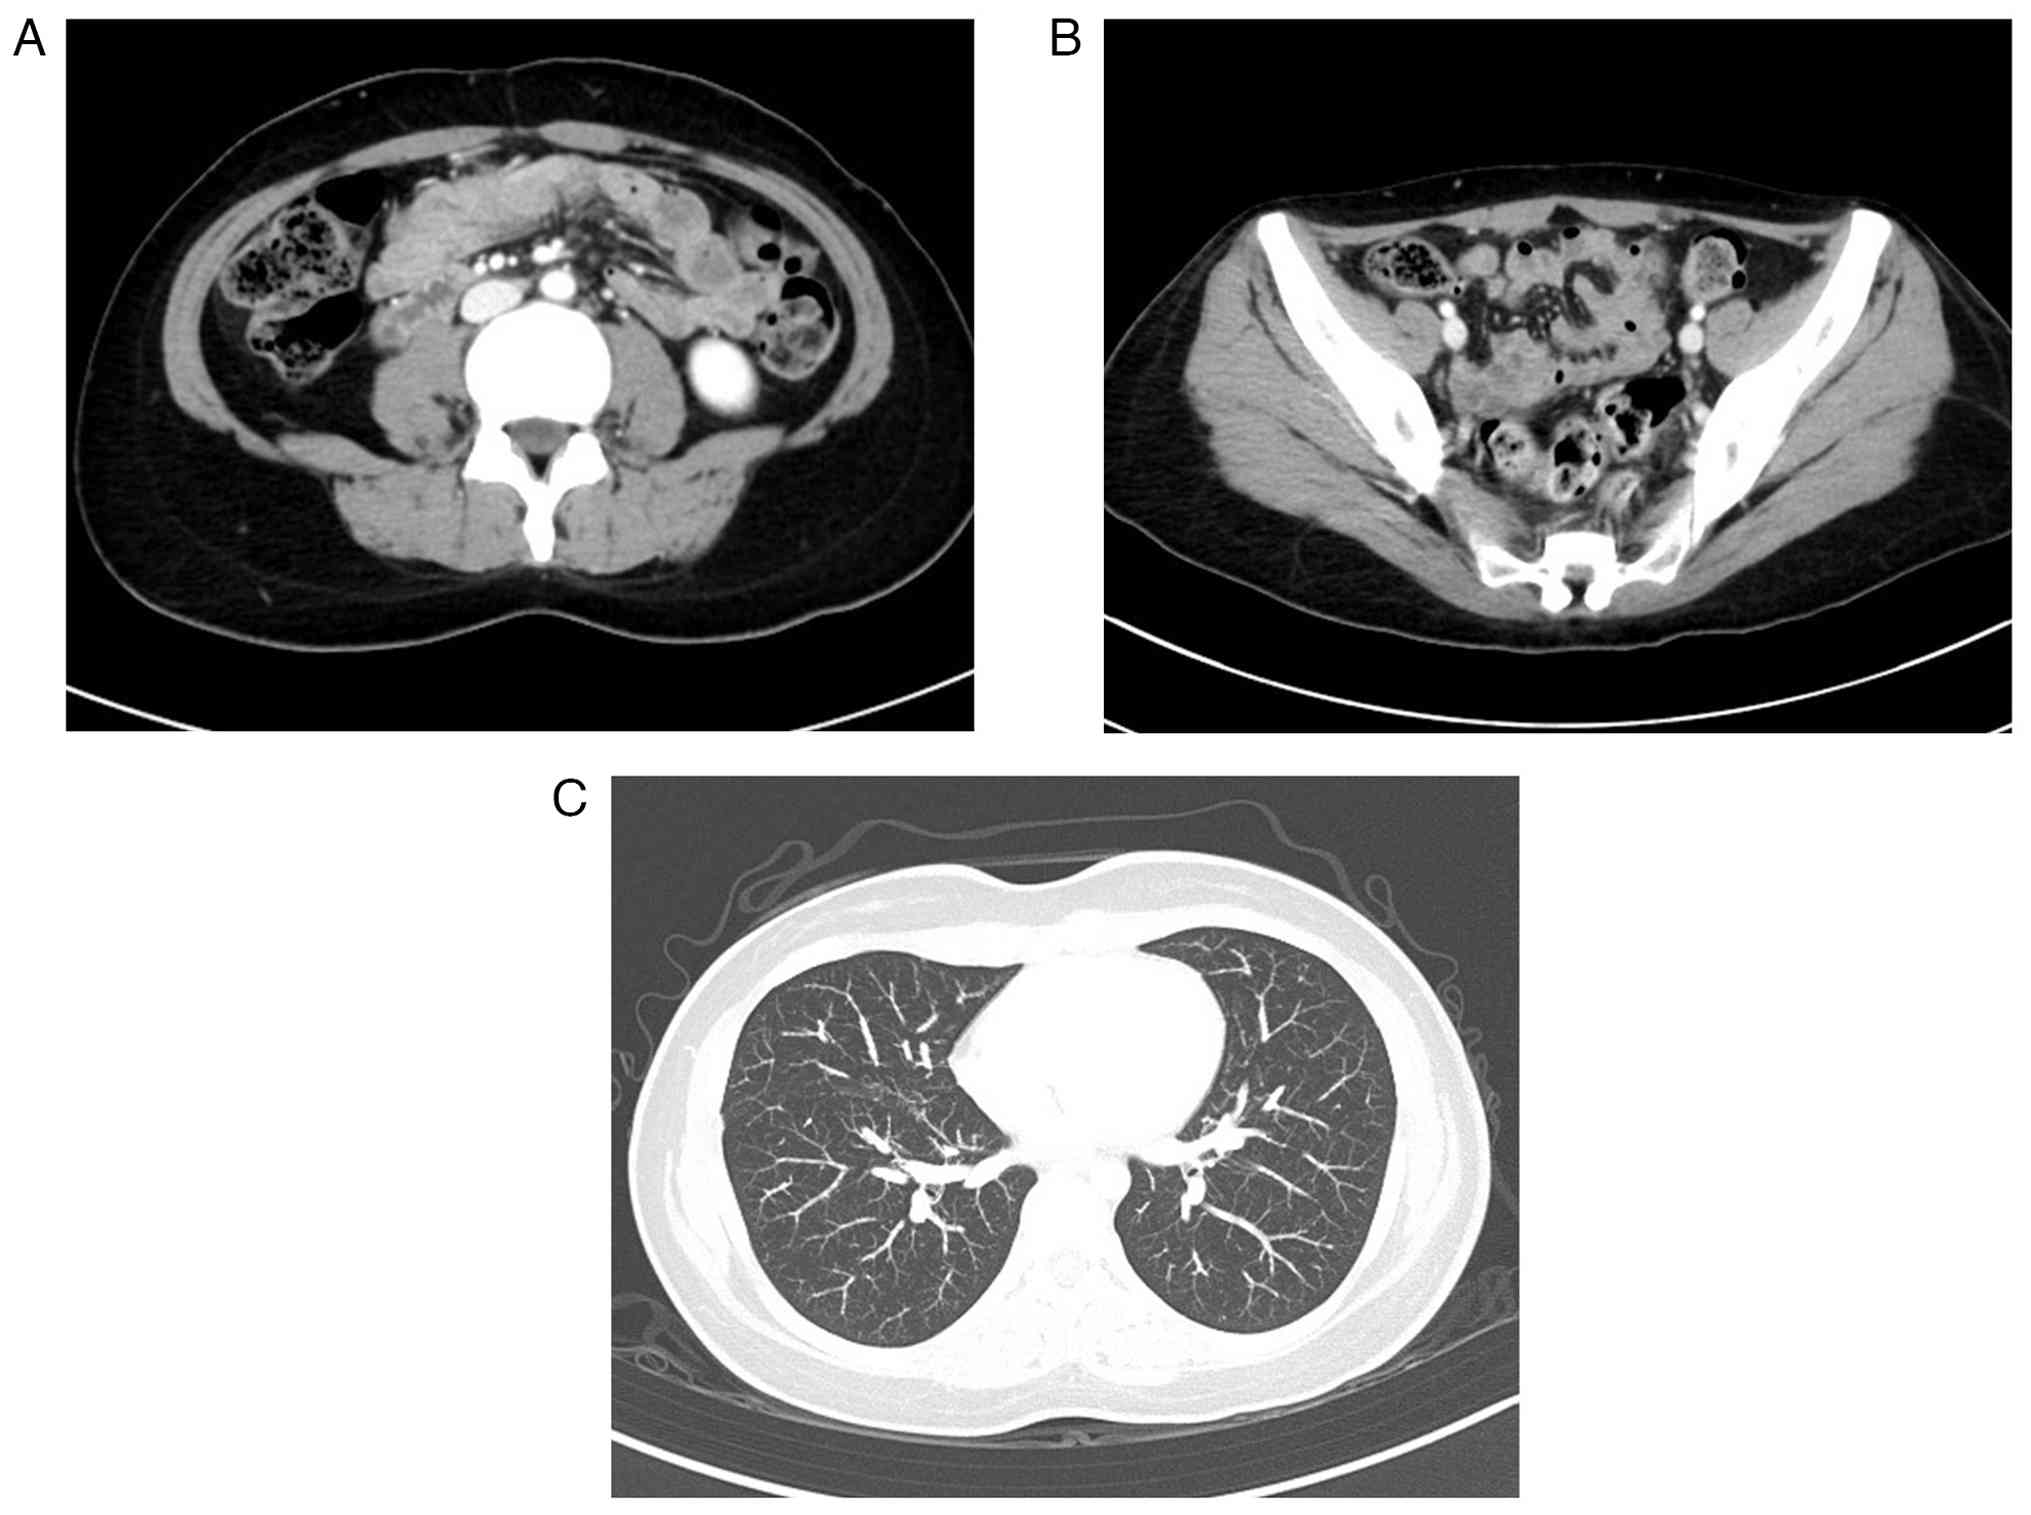

Pelvic magnetic resonance imaging revealed an irregular mass with mild contrast enhancement and restricted diffusion. This protruded from the myometrium into the uterine cavity (Fig. 1A-E). As both cervical and endometrial cytology were negative, a hysteroscopic biopsy of the tumor was performed. The tumor was white, irregular, and showed neovascularization (Fig. 2A). Endometrial biopsy revealed densely proliferating epithelioid cells with nuclear atypia and prominent mitoses, consistent with poorly differentiated carcinoma. However, atypical polygonal cells were also present. Immunohistochemistry showed reduced epithelial marker expression and weak positivity for smooth muscle markers, raising the possibility of carcinosarcoma (Fig. 2B-E). Computed tomography (CT) revealed para-aortic and pelvic lymph node metastasis and multiple pulmonary metastases (Fig. 3A-C). The patient underwent total hysterectomy with bilateral salpingo-oophorectomy to control genital bleeding and obtain a definitive diagnosis.

Computed tomography findings. (A)

Enlarged para-aortic lymph nodes (red arrow). (B) Enlarged pelvic

lymph nodes (red arrow). (C) Multiple pulmonary nodules (blue

arrows). These findings were suggestive of metastatic disease.

Computed tomography findings. (A) Enlarged para-aortic lymph nodes (red arrow). (B) Enlarged pelvic lymph nodes (red arrow). (C) Multiple pulmonary nodules (blue arrows). These findings were suggestive of metastatic disease.